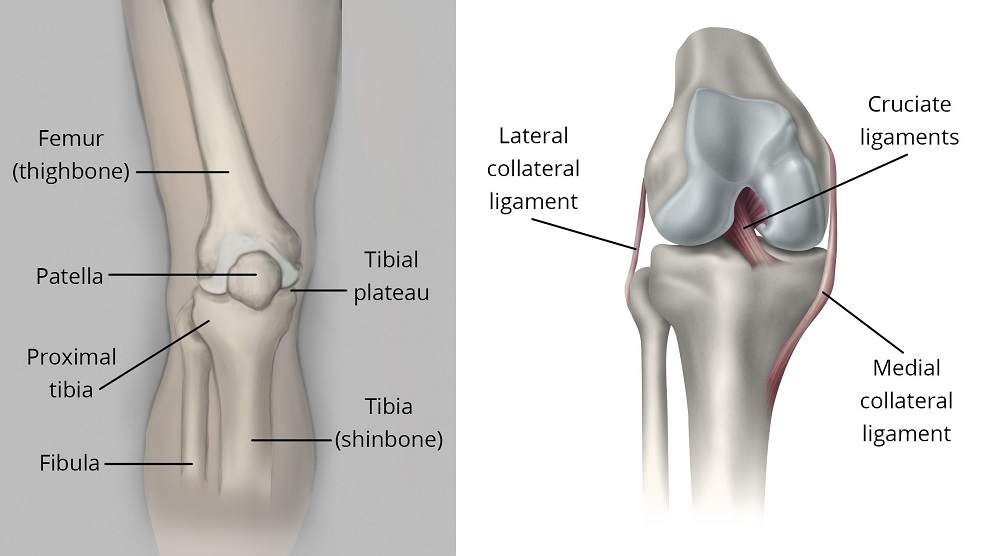

Illustration of knee anatomy, including the location of the proximal tibia

(Left) The proximal tibia is the upper portion of the bone, closest to the knee. (Right) Ligaments connect the femur to the tibia and fibula (kneecap not shown).

(Left) Reproduced from The Body Almanac. © American Academy of Orthopaedic Surgeons, 2003. (Right) J Bernstein, ed: Musculoskeletal Medicine. Rosemont, IL, American Academy of Orthopaedic Surgeons, 2003.

The knee is the largest weightbearing joint of the body. Two bones meet to form the knee joint:

• The femur (thighbone)

• The tibia (shinbone)

The kneecap sits in front of the joint to provide some protection.

Ligaments and tendons act like strong ropes to hold the bones together. They also work as restraints — allowing some types of knee movements, and not others. In addition, the way the ends of the bones are shaped helps to keep the knee properly aligned.